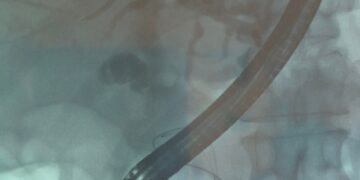

Laimei, yra daugybė seksualinių problemų, susijusių su urologinėmis ligomis, gydymo būdų, įskaitant dubens dugno terapiją, erekcijos priemones vyrams (pvz., geriamuosius vaistus, vakuuminius erekcijos prietaisus ir varpos implantus), gydymą, gerinantį makšties komfortą moterims ir sekso terapiją. poroms ir asmenims. Seksualinės medicinos specialistas gali suteikti pacientams prietaisus, vaistus ir (arba) gydymo būdus, kurie sumažina kai kurias seksualines problemas. Sekso terapija gali padėti pacientams ir jų partneriams spręsti jausmus, bendravimą ir seksualinę sąveiką, susijusią su seksualinės funkcijos pokyčiais, ir nustatyti, kaip elgtis intymiai.